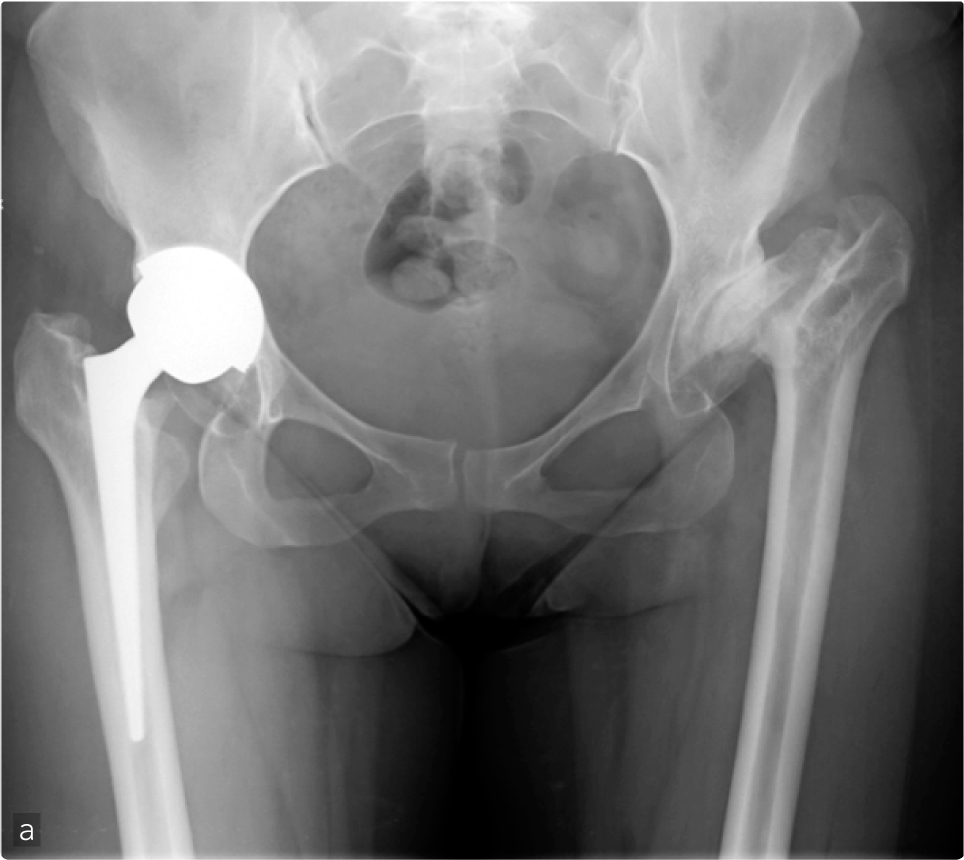

Femmina, 26 anni, necrosi della testa del femore. La grave coxartrosi le causava dolore resistente ad ogni terapia conservativa, zoppia di fuga e un severo accorciamento dell'arto inferiore sinistro (a-b). L'intervento di sostituzione protesica dell'anca è stato eseguito per via anteriore mini-invasiva (c). L'accesso chirurgico è stato eseguito con incisione cutanea orientata sulla piega della coscia ("Bikini") che rimane completamente nascosta dagli slip, sui piani profondi l'acceso intermuscolare ha permesso di raggiungere l'articolazione senza staccare nessun muscolo limitando il sanguinamento (nessuna trasfusione) e rendendo più rapido il recupero (deambulazione in seconda giornata post operatoria) (d).